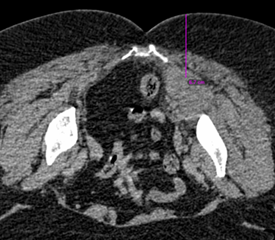

56 Y/ Female Patient Post op with Ca Breast on Chemotherapy; Complaining of pain in the right gluteal region and radiating till the right foot .

CT-guided aspiration of the right pyriformis abscess in prone position under local anesthesia.

Introducer needle used: 18G spinal needle ;

The patient was in extreme pain pre procedure which was better by 80 % post procedure as the mass effect of the abscess on the sciatic nerve had reduced considerably.